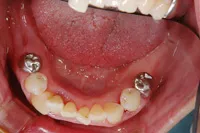

奥歯2本をインプラントで治療したケース

■治療前

■治療後

| 主訴 | 左下の歯が2本なくて咬みにくい 入れ歯はわずらわしいので嫌、金属の被せを白くしたい |

| 治療方法 | インプラント治療+補綴治療 |

| 治療期間 | 約1年 |

| 通院回数等 | 20回位 |

| 費用 | 約150万円 |

| リスク・副作用 | インプラント術後の腫れ・痛み |